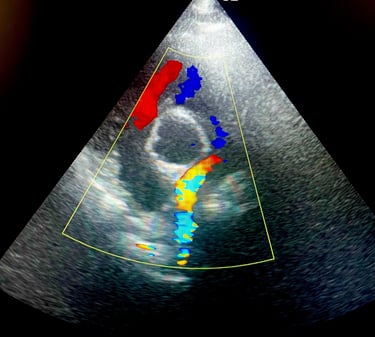

BADANIE ECHOKARDIOGRAFICZNE: badanie serca przy użyciu wysokiej klasy sprzętu ultrasonograficznego, który umożliwia wykrycie wad wrodzonych, chorób zwyrodnieniowych zastawek, powiększenia serca.